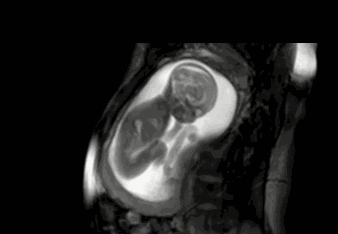

20周的时候是做大排畸检查,主要通过B超检查胎儿的面部是否存在畸形,通过设备看到宝宝丑陋的面部,通过医生讲解才知道,因为宝宝的皮下脂肪还比较少,所以看起来皱巴巴,以为宝宝不健康呢!